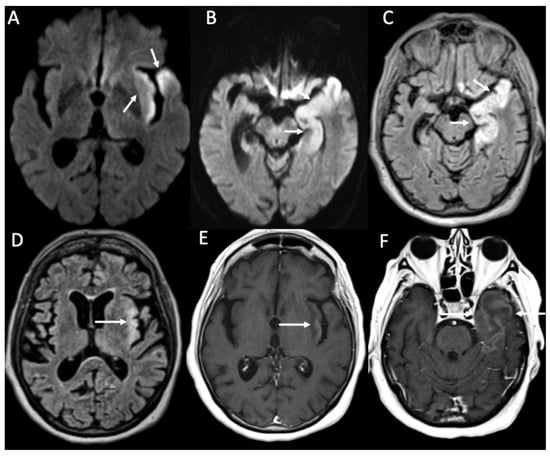

| Piogenic Meningitis | • Cerebrospinal fluid hyperintensity in T1 and FLAIR • Restricted diffusion of the subarachnoid spaces • Meningeal enhancement on T1 and FLAIR |

| Tuberculosis | • Leptomeningeal enhancement in the basal cisterns • Hydrocephalus very common • Infarcts in the basal ganglia due to vasculitis • Possible concomitant tuberculomas or miliary tuberculosis |

| Cryptococcus Neoformans | • Leptomeningeal enhancement • Cryptococcoma • Gelatinous pseudocysts |

| Candida albicans | • Microabscesses • Vascular lesions |

| Aspergillus fumigatus | • Abscesses • Vascular lesions |